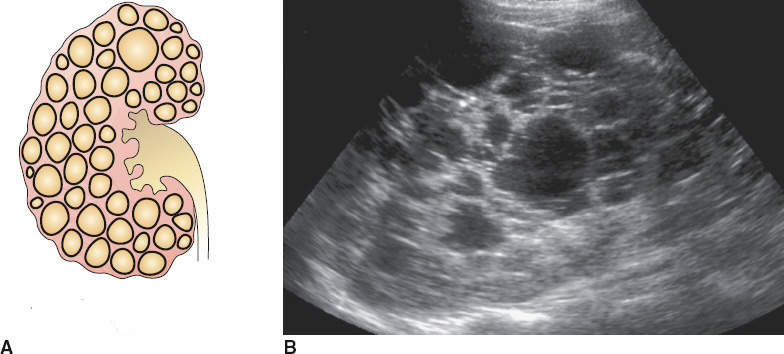

Arpkd, autosomal recessive polycystic kidney disease

Hereditary. Infants/children. Fatal. Renal failure & portal hypertension. Dilation of renal collecting tubules.

Arpkd, autosomal recessive polycystic kidney disease. Dilation of renal collecting tubules